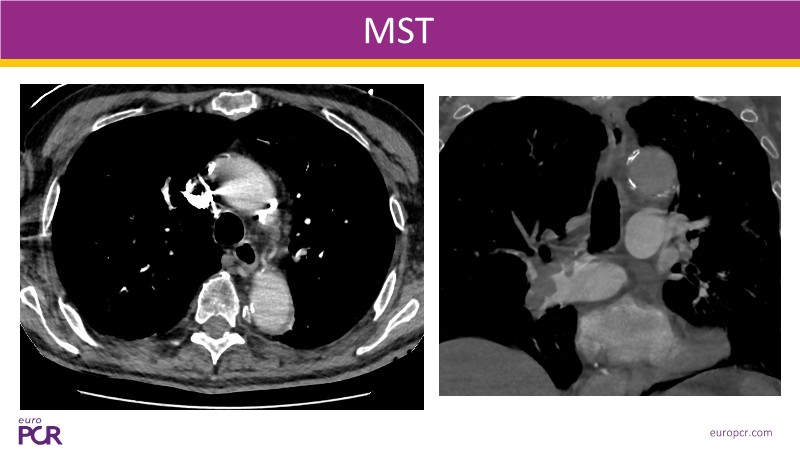

Watch this EuroPCR 2025 session on pulmonary embolism to explore the role of computer-assisted vacuum thrombectomy (CAVT) as an alternative to medical treatment in high-risk (massive) PE, supported by insights from the STRIKE PE study. Discover how CAVT rapidly and effectively offloads the right ventricle in intermediate-high-risk PE patients, especially those with a high bleeding risk. Review safety and efficacy data from a cohort of 450 patients demonstrating consistent procedural success. In short, this video provides a clear understanding of key procedural considerations, the latest evidence on Penumbra technology, and how ongoing innovation is shaping the future of PE management.